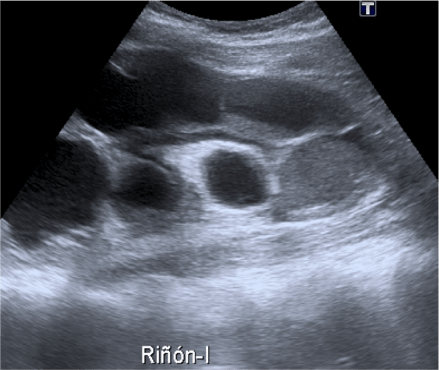

Arriba, se observa un quiste cortical simple con contenido anecogénico.